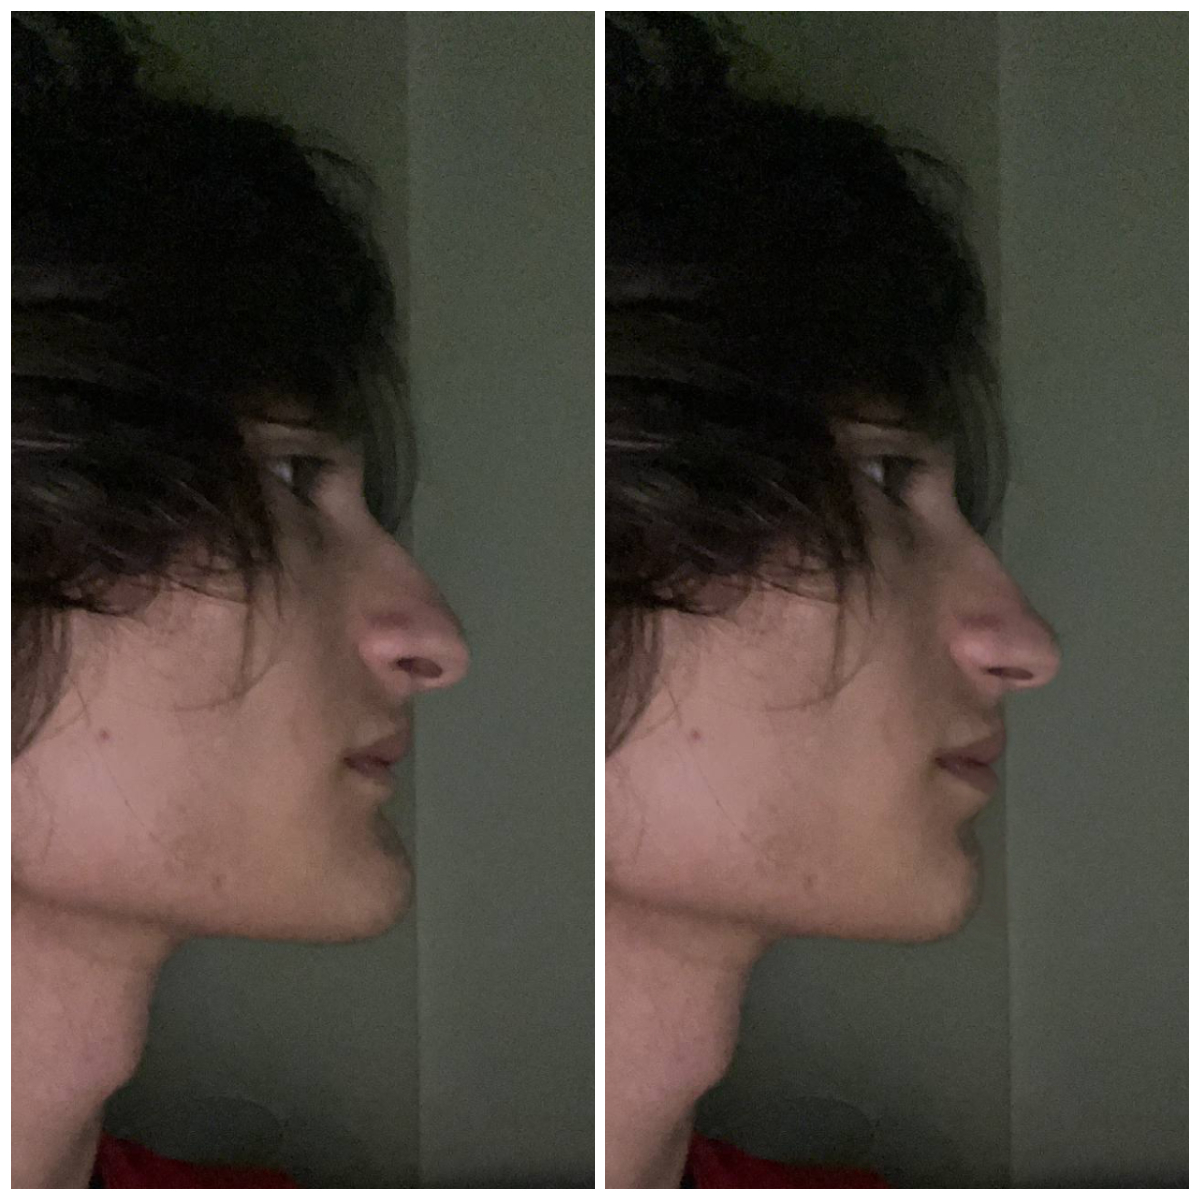

I need some advice! I have a deep and distal bite, and I've been thinking about bimax or lefort surgery, but my orthodontist said that it can be fixed with braces without surgery. The plan is to move the upper teeth slightly back and the lower teeth slightly forward to correct the bite, but I'm worried that moving the upper teeth will also move my maxilla, which is already flat. Should I be concerned about this? I want to receive valuable advice from experienced and knowledgeable individuals.

Rhino ik, Here's a photo:

I can take any necessary measurements of the bones.